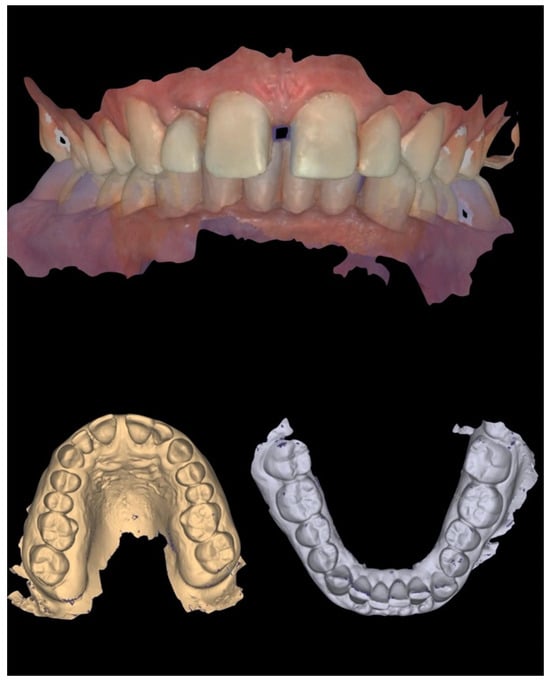

In addition to standard radiographs, a cone beam computed tomography (CBCT) scan was performed to obtain a three-dimensional assessment of the alveolar bone volume and morphology in the anterior maxillary region. Digital intraoral impressions were acquired using the Medit i500 scanner (MEDIT Corp., Seoul, Republic of Korea, Figure 2), complemented by intraoral and extraoral photographic records for comprehensive facial and dento-labial analysis (Figure 3 and Figure 4), as well as an aesthetic predictive simulation using digital smile design software (exocad’s DentalCAD 3.2 Elefsina, Smile Creator, exocad GmbH, Darmstadt, Germany).

Figure 2. Initial intraoral scans.